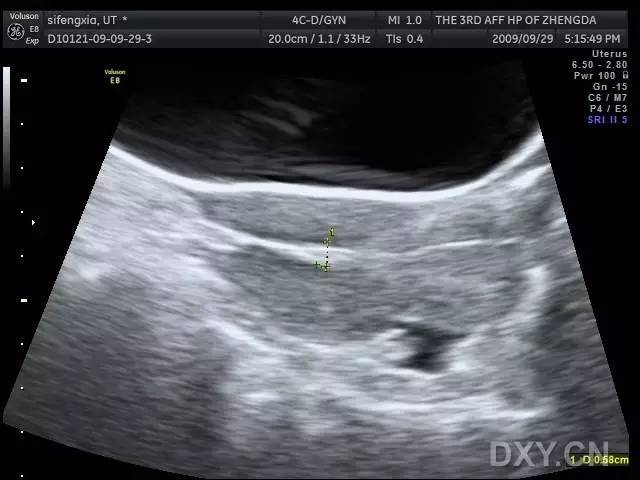

子宫穿孔超声表现图

子宫穿孔超声表现图,子宫穿孔超声图片

典型人流术子宫穿孔 - 超声医学讨论版 - 爱爱医医学

子宫穿孔的超声诊断

子宫穿孔超声图片

子宫穿孔b超图片